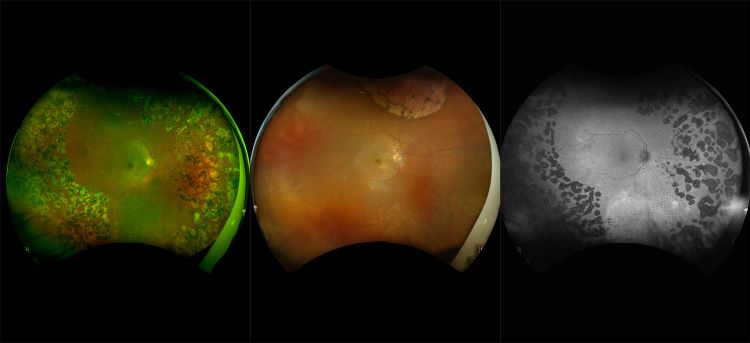

Diabetic eye disease is a complication of Diabetes Mellitus. Diabetic retinopathy is often detected as a complication, and it presents by affecting small blood vessels in the eye due to blockage or leakage. Over time, blood vessels can present as microaneurysms or hemorrhages or fluid (exudates). The number and severity of affected vessels determine the grade or retinopathy. There are 2 forms, nonproliferative (NPDR) and proliferative (PDR).

optomap imaging has been shown to improve the management of diabetes in patients. optomap images capture a 200° view (about 82%) of the retina versus the 75° view provided by 7SF images. Studies have shown that this wider view can uncover evidence of disease that is outside the narrow view of 7SF images. It can even change how doctors judge the severity of the disease. In addition, the latest study identified that 50% of the lesions were in the area outside of ETDRS and that in 13% of patients, these lesions suggested a more severe grade of retinopathy.

Evidence of disease at the periphery of the retina can also be a sign of future problems. Patients with peripheral DR lesions were more than four times more likely to see their DR get worse as compared to patients without lesions.

optomap imaging has demonstrated that diabetic lesions occur in the retinal periphery in up to 50% of eyes and these lesions might result in a more severe grade of retinopathy in 10% of eyes. Eyes with predominantly peripheral lesions (defined as outside of ETDRS 7 standard field) had a 4.7 fold increased risk of progression to proliferative diabetic retinopathy (PDR). Eyes with predominantly peripheral lesions had a 3.2 fold risk of 2 step progression in DR.

optomap Multimodal Diabetic Eye Disease Cases

Optos offers multimodal imaging with all ultra-widefield devices. Having both ultra-widefield and four images captured in less than one second has been shown to enhance pathology detection and disease management as well as improve practice and clinic flow. Ultra-widefield multimodal imaging is important across all access points of patient care - screening, detection, diagnosis, and treatment.